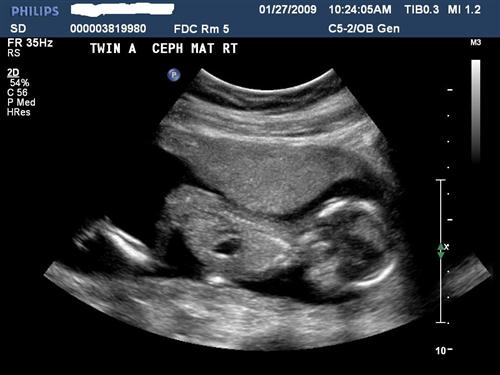

14.5 weeks

Twin A - 14.5 wks